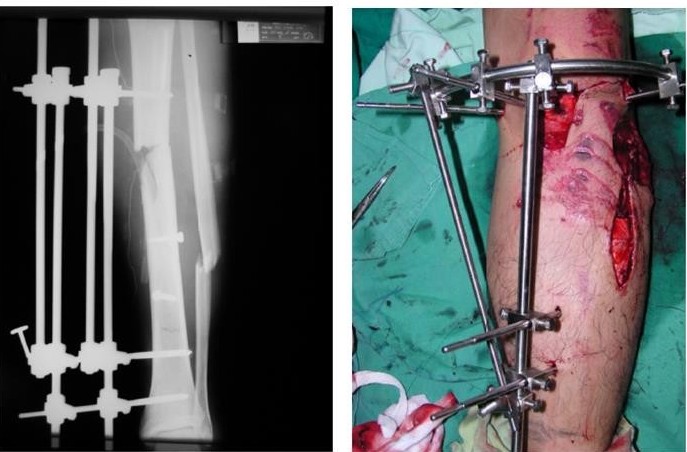

- Phẫu thuật:

- Nẹp vít (AO)

- Đinh nội tủy

- Buộc chỉ thép, xuyên đinh

- Ghép xương

Ưu điểm của phẫu thuật là cho phép nắn xương đúng vị trí, bất động tương đối chắc chắn, tránh được di lệch thứ phát, người bệnh có thể tập cử động và chịu trọng lượng sớm, tránh các biến chứng teo cơ, cứng khớp, loãng xương.